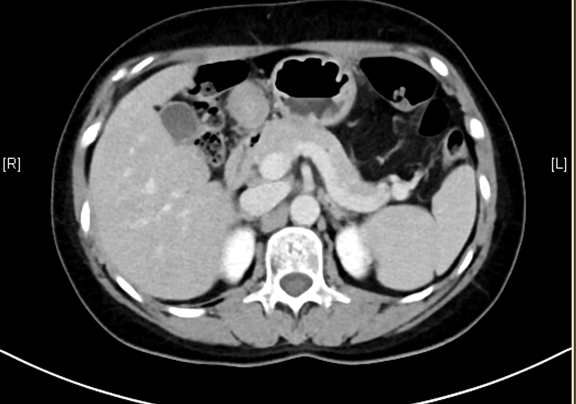

下腹部增强CT示:肝左外叶肝癌可能性大; 肝左内叶及右后叶海绵状血管瘤可能性大。

术前CT检查:

动脉期

静脉期

平衡期